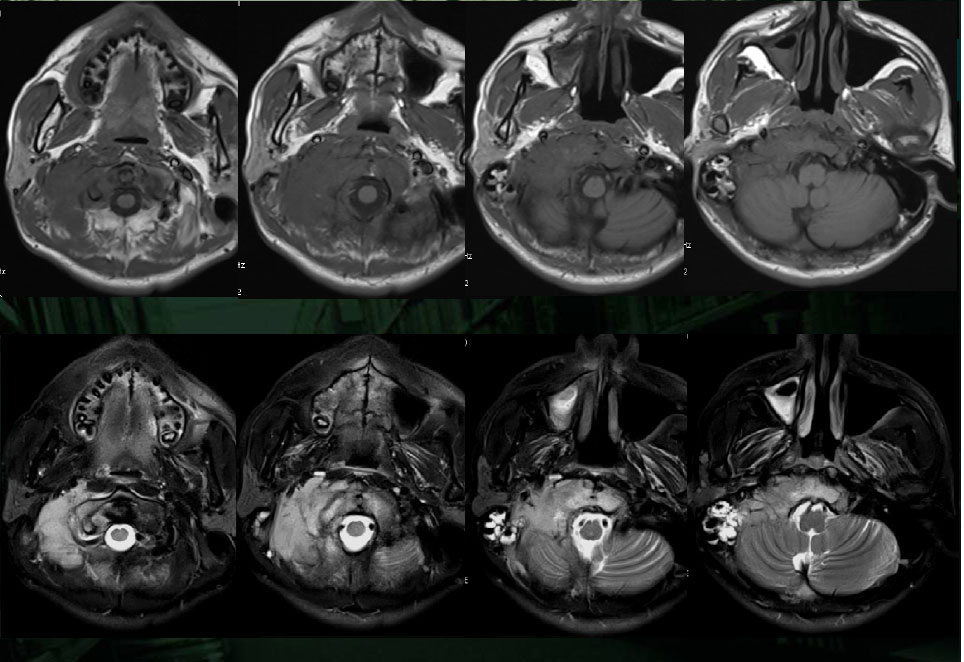

男性,20岁。

颈部疼痛2月,腰部臀部疼痛1月。

On T1WI, the tumor demonstrated isointensity or slightly hypointensity; on T2WI, the tumor demonstrated heterogeneous hyperintensity.

The tumor demonstrated heterogeneous enhancement on contrast-enhanced CT/T1WI.

Cystic necrotic component and haemorrhagic change are usually obvious.